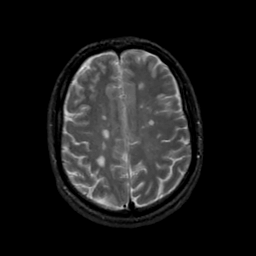

MR Study #19, August 25, 1991 -- Slice #36